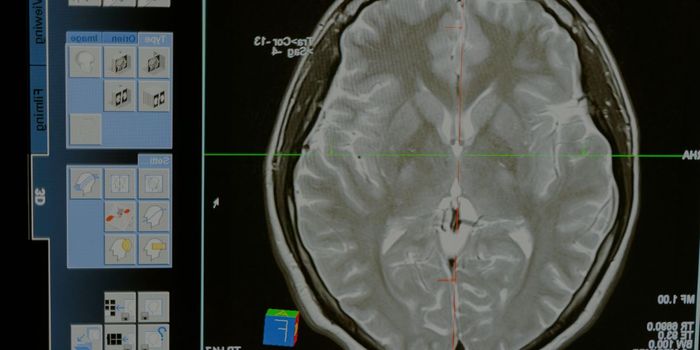

AUG 26, 2024NeuroscienceA groundbreaking study published in the New England Journal of Medicine has demonstrated the remarkable potential of bra ...